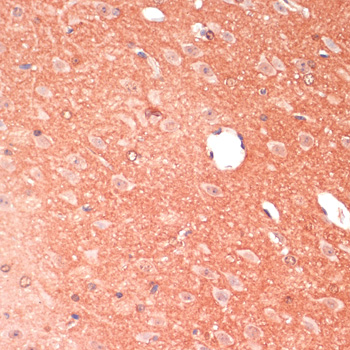

Immunohistochemistry of paraffin-embedded mouse brain using GAP43 antibody.

Immunohistochemistry of paraffin-embedded rat brain using GAP43 antibody.